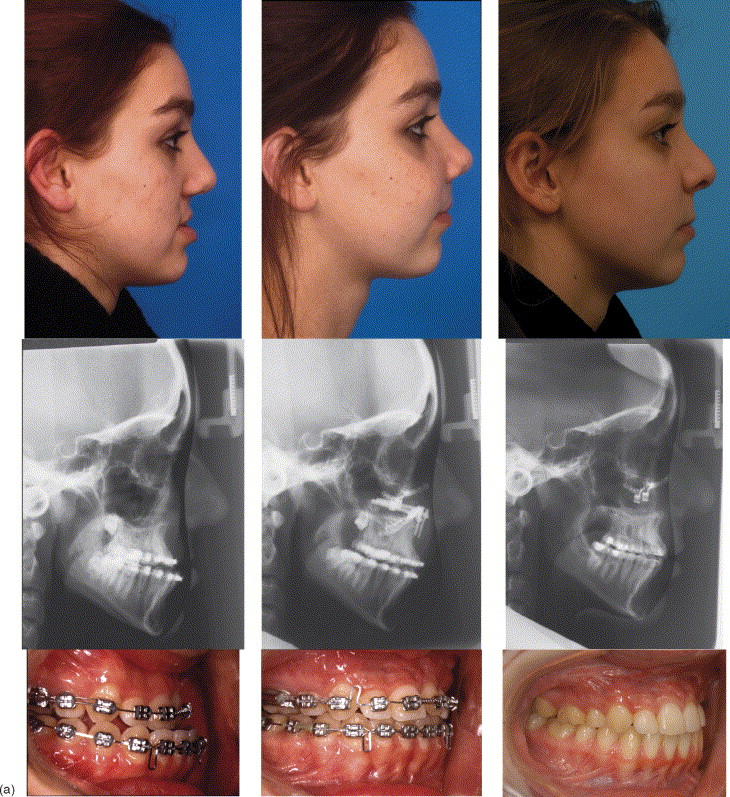

2. QUADANGULAR LEFORT + BSSO + GENIOPLASTY

quadangular lefort less risky than MLF3/LF2)

2. QUADANGULAR LEFORT + BSSO + GENIOPLASTY

quadangular lefort